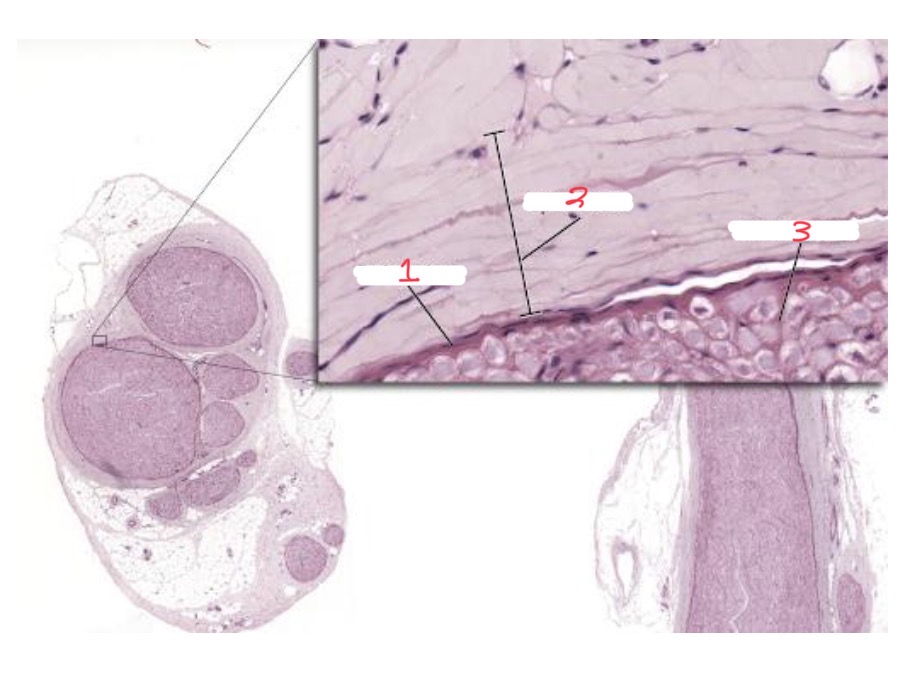

1

Scala vestibuli

2

Internal spiral sulcus

3

Vestibular membrane

4

hair cells

5

Tectorial membrane

6

Osseus spiral lamina

7

Spiral ganglion

8

Scala tympani

9

Organ of corti

10

Basilar membrane

11

spiral ligament

12

Cochlear duct

What is this

Cochlear cross section